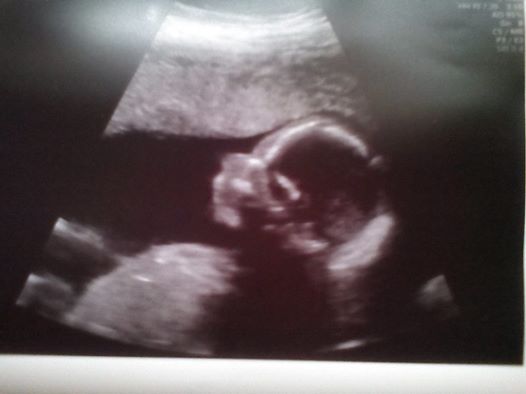

Ajko to je nadherna princezna. Gratulujuuuuu